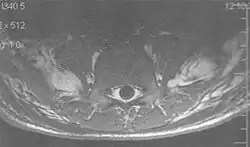

Metal artifacts occur at interfaces of tissues with different magnetic susceptibilities, which cause local magnetic fields to distort the external magnetic field. This distortion changes the precession frequency in the tissue leading to spatial mismapping of information. The degree of distortion depends on the type of metal (stainless steel having a greater distorting effect than titanium alloy), the type of interface (most striking effect at soft tissue-metal interfaces), pulse sequence and imaging parameters. Metal artifacts are caused by external ferromagnetics such as cobalt containing make-up, internal ferromagnetics such as surgical clips, spinal hardware and other orthopaedic devices, and in some cases, metallic objects swallowed by people with pica.[3] Manifestation of these artifacts is variable, including total signal loss, peripheral high signal and image distortion (Figs 3 and 4).[1] Reduction of these artifacts can be attempted by orientating the long axis of an implant or device parallel to the long axis of the external magnetic field, possible with mobile extremity imaging and an open magnet. Further methods used are choosing the appropriate frequency encoding direction, since metal artifacts are most pronounced in this direction, using smaller voxel sizes, fast imaging sequences, increased readout bandwidth and avoiding gradient-echo imaging when metal is present. A technique called MARS (metal artifact reduction sequence) applies an additional gradient, along the slice select gradient at the time the frequency encoding gradient is applied.